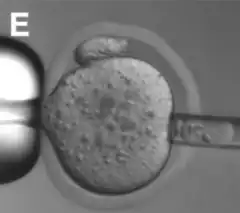

El corpúsculo polar de la primera división meiótica (primer cuerpo polar o 1pb) se ubica dentro de los 90° del lugar donde se encuentran los cromosomas en Metafase de la segunda meiosis (metafase meiótica II o MII), lo que permite su localización durante la manipulación en el laboratorio.[7]

La "biopsia de cuerpo polar" se puede utilizar en embriología para predecir la viabilidad y la probabilidad de embarazo del ovocito del que fue tomado.[3] El método de estudio utilizado, llamado arrays de Hibridación Genómica Comparada (aCGH) consiste en extraer el cuerpo polar de un ovocito que va a ser utilizado y analizarlo para ver sus cromosomas.[8]